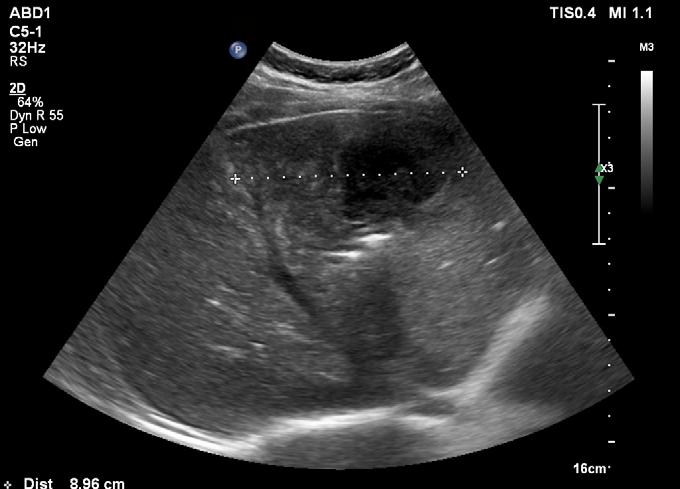

Stabilirea indicaţiei tratamentului endovascular cu DEBDOX necesită o pre-evaluare CT (“triple-phase”) sau IRM cu contrast, coroborată cu manifestările clinice și a datelor de laborator (AFPdeterminare cantitativă folosită ulterior în dinamica pentru evaluare, follow-up). Fiecare flacon de microsfere va fi încărcat cu 50-75 mg de Doxorubicin (doza de încărcare 25-37,5 mg Doxorubicin/ ml de microsfere)

Leziunea ideală pentru tratamentul prin radiofrecvență are diametrul sub 3 cm și este situată la distanță de capsula hepaticã, pediculi portali sau vene hepatice [84]

O zonă de ablație suficientă pentru un tratament curativ fară riscuri semnificative se poate obține în cazul nodulilor <5 cm (cu minim 2 aplicații) și a maxim 4 noduli <3 cm.

• Ablația tumorală hepatică cu microunde (MWA) utilizează căldura din energia microundelor pentru a distruge celulele canceroase hepatice. Pentru a realiza procedura, este introdus pe cale percutană un ac în tumora hepatică, sub ghidaj imagistic, ecografic sau CT. Se știe că celulele maligne sunt mai sensibile la leziunile prin hipertermie decât celulele normale , ca urmare creșterea temperaturii intatumorale prin curentii MWA vor distruge tumora.